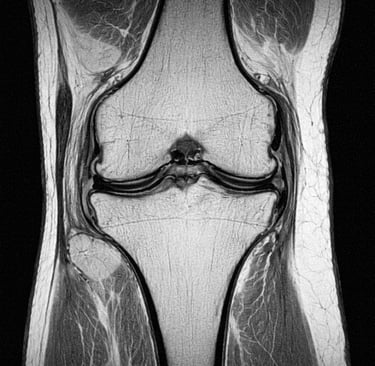

L’IRM du genou est un examen d’imagerie médicale qui permet d’analyser en détail les structures internes du genou.

L’IRM (Imagerie par Résonance Magnétique) est un examen qui utilise un champ magnétique pour obtenir des images précises du genou.

Elle permet de visualiser :

les ménisques

les ligaments

le cartilage

les tendons

l’os

Contrairement à la radiographie, elle permet d’explorer les tissus mous.

Que montre une IRM du genou

L’IRM permet de détecter :

lésions du ménisque

rupture des ligaments

arthrose du genou

inflammation articulaire

épanchement de synovie

C’est un examen très précis pour le diagnostic.